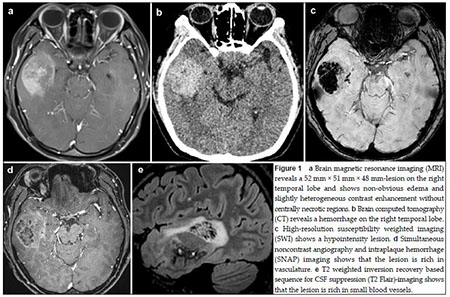

20170512093522 Figure 1 a Brain magnetic resonance imaging (MRI) reveals a 52 mm × 51 mm × 48 mm-lesion on the right temporal lobe and shows non-obvious edema and slightly heterogeneous contrast enhancement without centrally necrotic regions.b Brain computed tomography (CT) reveals a hemorrhage on the right temporal lobe. c High-resolution susceptibility weighted imaging (SWI) shows a hypointensity lesion.d Simultaneous noncontrast angiography and intraplaque hemorrhage (SNAP) imaging shows that the lesion is rich in vasculature.e T2 weighted inversion recovery based sequence for CSF suppression (T2 Flair)-imaging shows that the lesion is rich in small blood vessels.

20170512093557 Figure 2 a The lesion,as observed during the surgical procedure,shows distinct boundaries with reddish brown appearance and is rich in venous vessels.b Histopathological analysis reveals that the tumor is composed of densely packed cells and shows nuclear and cell pleomorphism.The histopathological diagnosis is glioblastom.(Hematoxylin-eosin stain,×100)